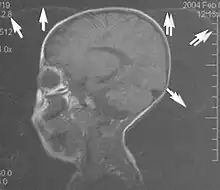

Motion artifacts

A motion artifact is one of the most common artifacts in MR imaging.[2] Motion can cause either ghost images or diffuse image noise in the phase-encoding direction. The reason for mainly affecting data sampling in the phase-encoding direction is the significant difference in the time of acquisition in the frequency- and phase-encoding directions.[1] Frequency-encoding sampling in all the rows of the matrix (128, 256 or 512) takes place during a single echo (milliseconds). Phase-encoded sampling takes several seconds, or even minutes, owing to the collection of all the k-space lines to enable Fourier analysis. Major physiological movements are of millisecond to seconds duration and thus too slow to affect frequency-encoded sampling, but they have a pronounced effect in the phase-encoding direction. Periodic movements such as cardiac movement and blood vessel or CSF pulsation cause ghost images, while non-periodic movement causes diffuse image noise (Fig. 1). Ghost image intensity increases with amplitude of movement and the signal intensity from the moving tissue. Several methods can be used to reduce motion artifacts, including patient immobilisation, cardiac and respiratory gating, signal suppression of the tissue causing the artifact, choosing the shorter dimension of the matrix as the phase-encoding direction, view-ordering or phase-reordering methods and swapping phase and frequency-encoding directions to move the artifact out of the field of interest.[1]